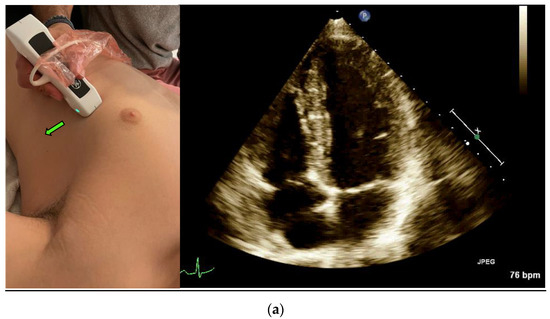

Left ventricular (LV) Ejection Fraction is an important clinical index. EF assessment can be extremely valuable in evaluating hemodynamically unstable patients [12] and dyspneic patients [4]. It can also diagnose heart failure in different settings, such as the emergency department and the internal wards [13,14]. The classic method for measuring EF is the Simpson method, which requires manually tracing the endocardial border of the left Ventricle in systole and diastole in both the apical four-chamber view (Figure 1a) and the apical two-chamber view (Figure 1c) [15].

Figure 1.

(a) Acquisition and anatomy of the Apical Four Chamber View. (b) Acquisition and anatomy of the Apical Five Chamber View (similar acquisition to Apical Four Chamber View, with a slight upward tilt of the probe). (c) Acquisition (probe point—green arrow) and anatomy of the Apical Two Chamber View.